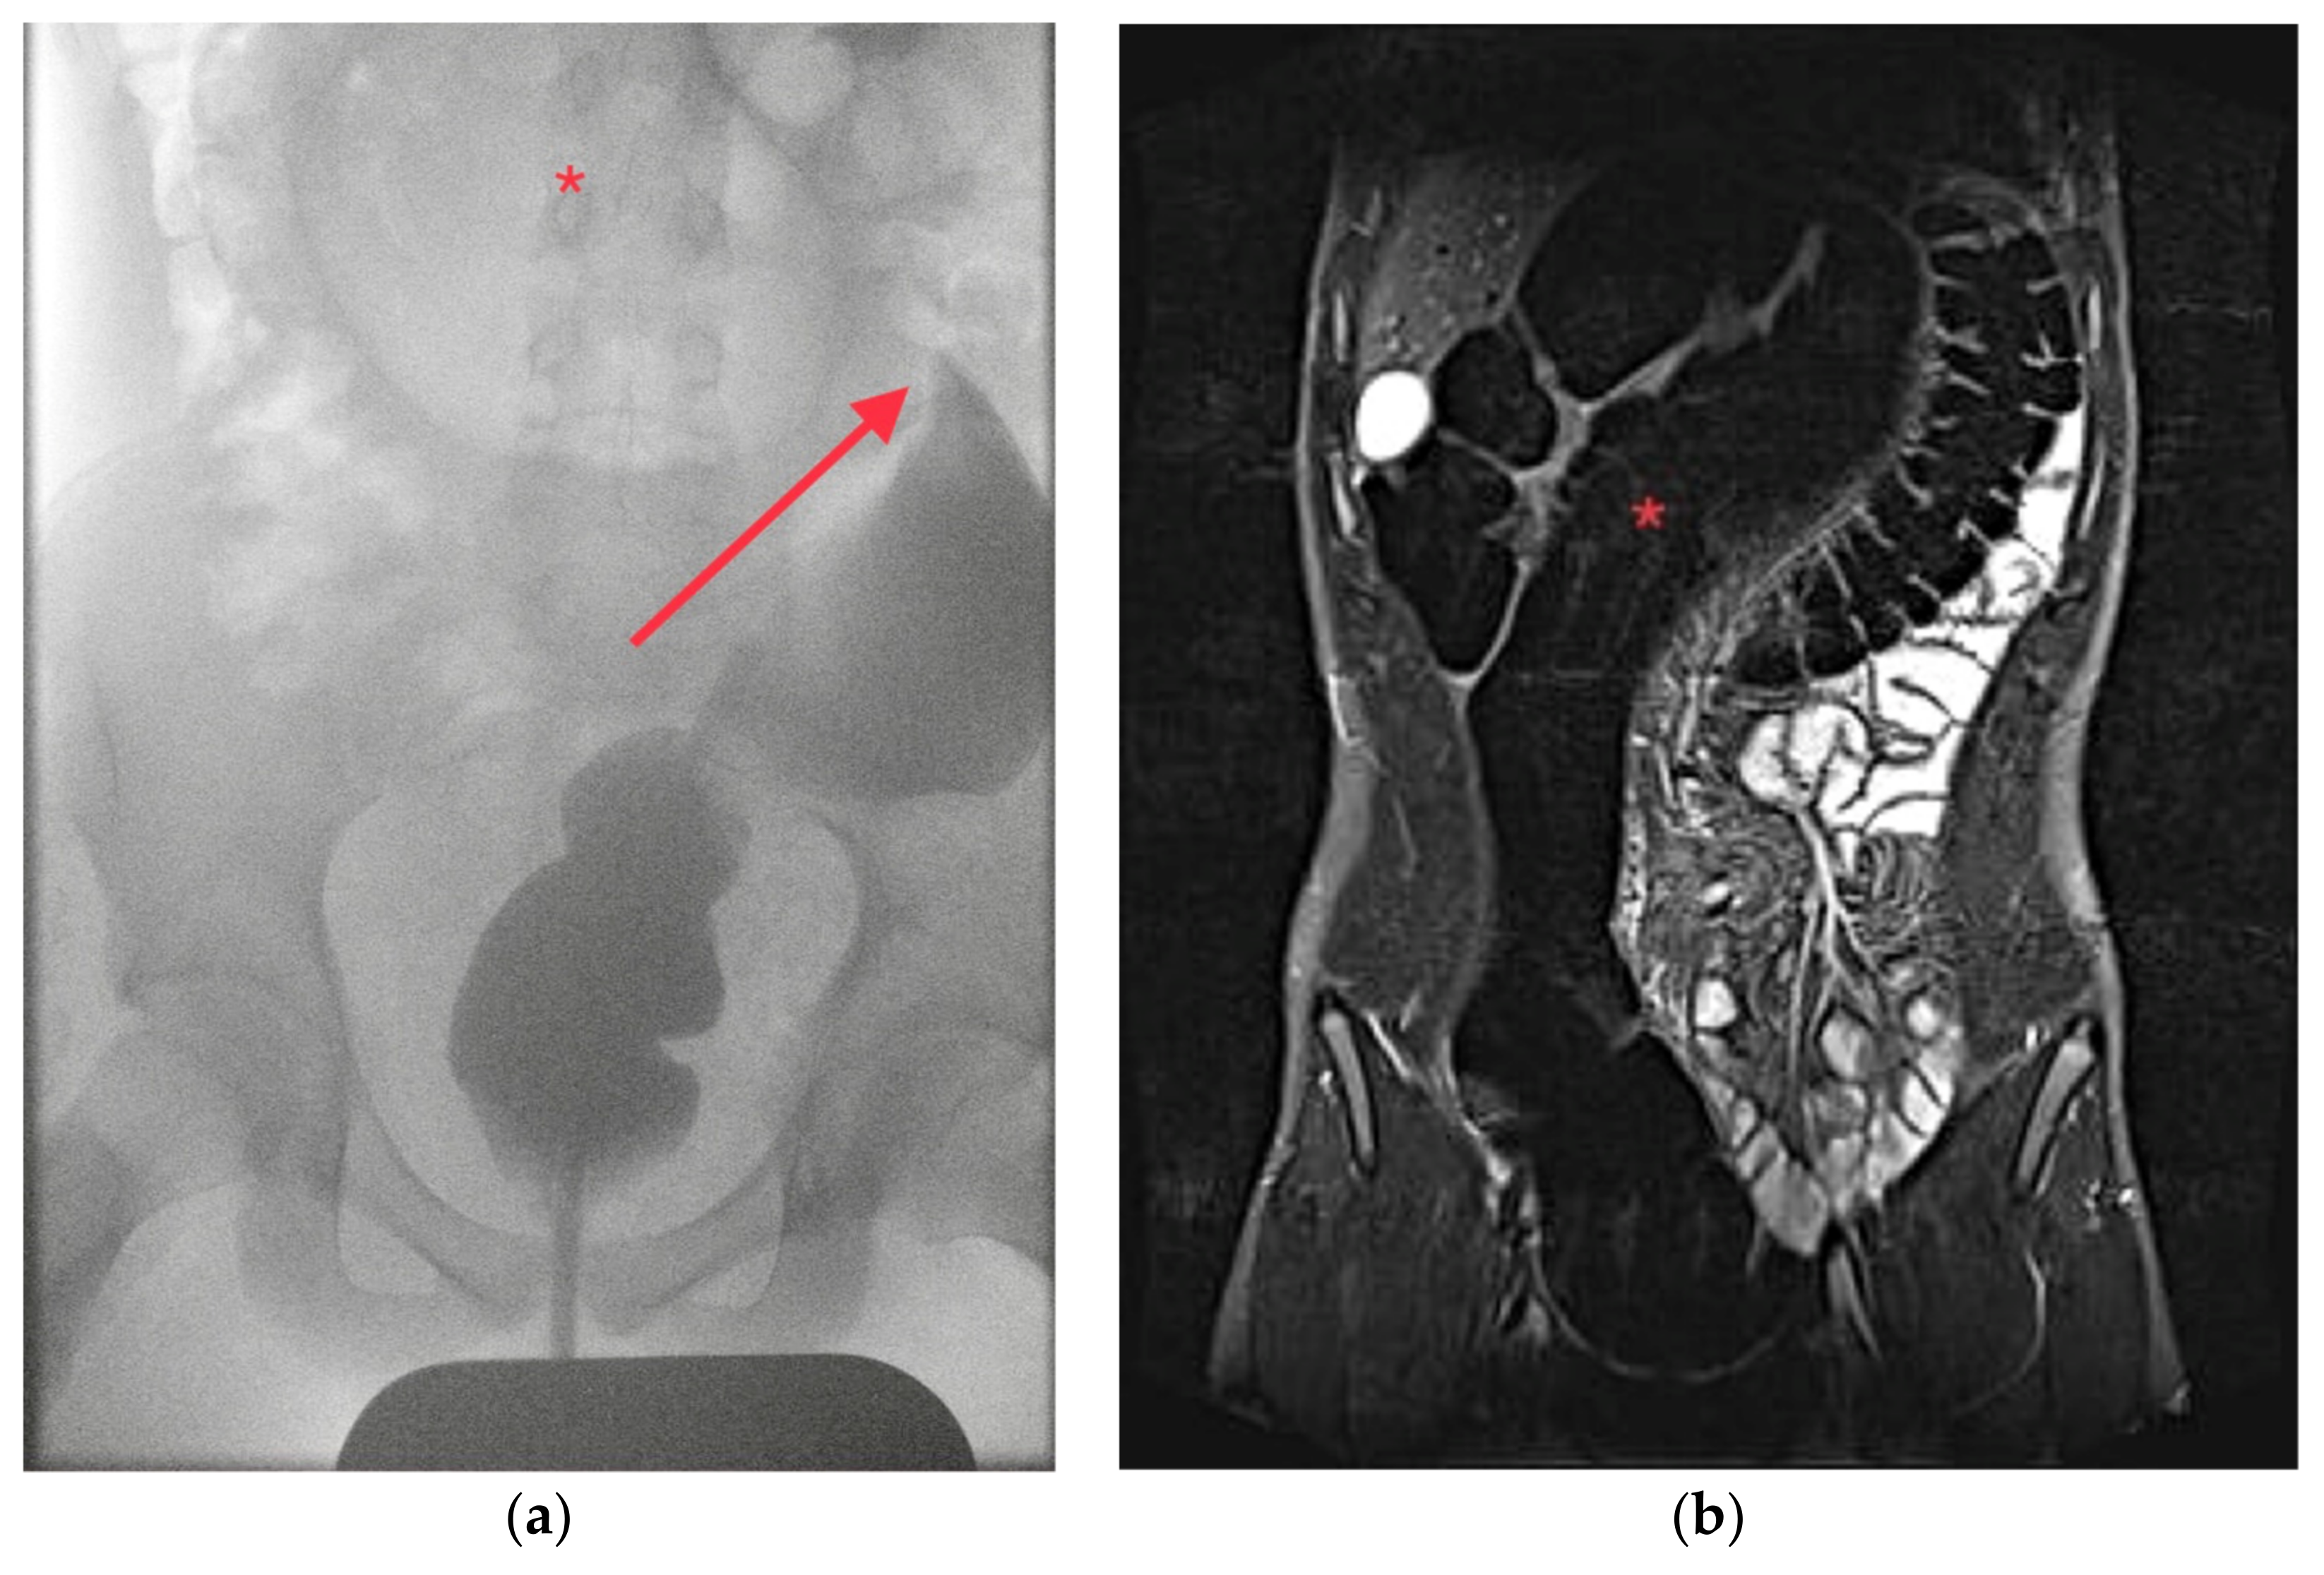

A 14-year-old adolescent boy presented to our interdisciplinary pediatric emergency department with severe colicky abdominal pain since the day before. The abdomen was distended and mildly tender without guarding. The medical history was without any hints for HD or chronic constipation. Ultrasound showed dilated, air-filled bowel loops, so an abdominal radiograph was performed suspecting LBO. The radiographic findings were pathognomonic for SV without signs of perforation. A decompression with a large bore rectal tube could be performed. Upon request by the parents, the patient was discharged home with recommendation for a follow-up visit a few days later, including a diagnostic work-up. However, the patient presented again the next day with similar abdominal pain and a radiograph confirmed the recurrent SV. Another decompression by rectal tube was attempted but was only successful after performing a contrast enema under fluoroscopy. (Figure 2a). Two days later, the patient presented one more time with the same symptoms, and again, decompression under fluoroscopy with a contrast enema was successful. The patient was admitted and underwent an MRI and a colonoscopy to rule out any rare anatomic conditions or neoplasms like polyps causing the uncommon finding of SV without any prior history of constipation. HD was considered highly unlikely so rectal biopsies were omitted. The MRI showed a considerably large and thick sigmoid (Figure 2b).

Figure 2. Patient 2: (a) Contrast enema showing the air-filled, dilated sigmoid (*) and the ‘bird’s beak-sign’ (arrow); (b) MRI showing a grossly enlarged and dilated sigmoid (*).